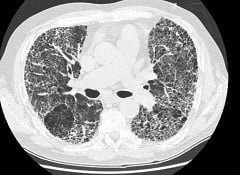

Средостение, расположенное между легкими, играет ключевую роль в функционировании органов грудной клетки. Врачи подчеркивают важность его анатомии и физиологии для диагностики различных заболеваний. Например, увеличение лимфатических узлов в средостении может указывать на инфекционные или онкологические процессы. Специалисты также отмечают, что средостение может быть затронуто при травмах, что требует внимательного подхода к диагностике и лечению. Современные методы визуализации, такие как КТ и МРТ, позволяют врачам более точно оценивать состояние средостения и выявлять патологии на ранних стадиях. Важно, чтобы пациенты обращались за медицинской помощью при появлении симптомов, таких как кашель или боль в груди, так как это может быть связано с проблемами в этой области.

Лимфаденопатия (увеличение лимфатических узлов) средостения наблюдается, как правило, при лимфомах, метастазах карциномы и некоторых других неопухолевых заболеваниях (туберкулез, саркоидоз и проч.).